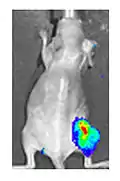

Both in the laboratory and in the clinic it is useful to have a simple means of identifying cells infected by the experimental virus. This can be done by equipping the virus with "reporter genes" not normally present in viral genomes, which encode easily identifiable protein markers. One example of such proteins is GFP (green fluorescent protein) which, when present in infected cells, will cause a fluorescent green light to be emitted when stimulated by blue light.[87][88] An advantage of this method is that it can be used on live cells and in patients with superficial infected lesions, it enables rapid non-invasive confirmation of viral infection.[89] Another example of a visual marker useful in living cells is luciferase, an enzyme from the firefly which in the presence of luciferin, emits light detectable by specialized cameras.[87]

Addition of the sodium-iodide symporter (NIS) gene to the viral genome causes infected tumour cells to express NIS and accumulate iodine. When combined with radioiodine therapy it allows local radiotherapy of the tumour, as used to treat thyroid cancer. The radioiodine can also be used to visualise viral replication within the body by the use of a gamma camera.[87] This approach has been used successfully preclinically with adenovirus, measles virus and vaccinia virus.[94][95][96]